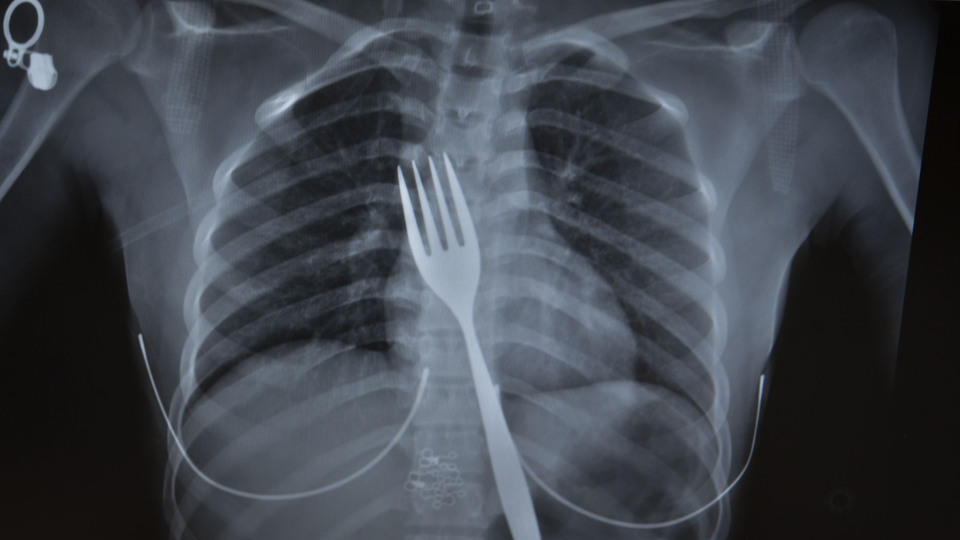

Burada röntgeni çekilen hastanın yemek borusunda 18 santimlik çatal olduğu tespit edildi.

Vakayı ilk duyduğunda şaşırdığını anlatan Edizsoy, "Büyük bir çatalın tamamen yutulması şeklinde ortaya çıkan bu vakayı ilk duyduğumda doğru olmadığını düşündüm. Hasta 18 yaşında ve yabancı uyrukluydu. Türkçesi biraz zayıf olduğu için belki de yanlış anlaşılmalar olabileceğini düşündük. Ama hastanın filmini çektiğimizde gerçekten bir çatalın yemek borusunda olduğunu gördük" dedi.